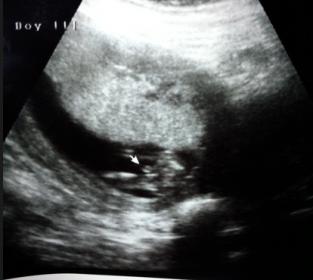

14weeks 5days What do you think? :)

I know that 14 weeks is early to do a gender determination test! But my boyfriend and I were very excited to find out so we went to see anyways!

We were told boy which is awesome!!! But since we did it so early I wanted to post some pictures and see if anyone had similar photos or just wanted to let us know what they think! After coming home and doing some research and comparing of ultrasounds, I read that a lot of times you can't tell at this period because the boy and girl parts look very similar. Let us know what you think! Either way we are very blessed!